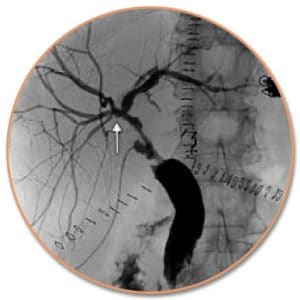

Τα εργαστηριακά και τα κλινικά ευρήματα των καλοήθων στενώσεων των χοληφόρων ομοιάζουν μ’ εκείνα της μεθηπατικής χολόστασης. Όχι σπάνια, εκδηλώνονται με υποτροπιάζοντα επεισόδια σηπτικής χολαγγειίτιδας, που χαρακτηρίζονται από πυρετό, ίκτερο, ρίγος, κνησμό και επιγαστρικό πόνο. Δευτερογενώς, αναπτύσσεται λιθίαση στην προστενωτική περιοχή λόγω της χολικής στάσης. Επί μακροχρόνιας διάρκειας της νόσου, αναπτύσσεται δευτεροπαθής χολική κίρρωση.Η ERCP είναι η πιο διαφωτιστική και κατατοπιστική μέθοδος για τη διάγνωση και την αντικειμενική αξιολόγηση του μεγέθους του προβλήματος, γιατί αναδεικνύει με ευκρινή τρόπο το ύψος, το μήκος, τη μορφολογία και πιθανόν την αιτία (π.χ. clips) της στένωσης. Όταν για ανατομικούς λόγους δεν είναι εφικτή η πραγματοποίηση της ERCP η διαδερμική διηπατική χολαγγειογραφία (PTC) παρέχει τις πιο χρήσιμες πληροφορίες. Σημαντικά είναι τα ευρήματα που αποκομίζονται από το υπερηχογράφημα (κλασικό και ενδοσκοπικό), την αξονική τομογραφία, την μαγνητική τομογραφία και την MRCP.

Η ERCP, από μόνη της ή σε συνδυασμό με τη διαδερμική διηπατική χολαγγειογραφία, αποτελεί πολύτιμη εξέταση, επειδή αποκαλύπτει με ευκρίνεια το είδος της βλάβης και τις εγκατεστημένες ανατομικές μεταβολές. Εφόσον διαπιστωθεί πλήρης διατομή ή εντελώς απόφραξη της κύριας χοληφόρου οδού, ο ασθενής παραπέμπεται για χειρουργική επιδιόρθωση σε χειρουργικό κέντρο με την δέουσα εμπειρία. Ο συχνότερος τύπος επέμβασης που γίνεται στις περιπτώσεις αυτές είναι η Roux-en-Y υψηλή ηπατικονηστιδική αναστόμωση, με ελεύθερη έλικα νήστιδας διαμεσοκολικά ανασπώμενη, σύμφωνα με την τεχνική που περιγράφηκε από τους Hepp και Couinaud. Οι επεμβάσεις αυτές χαρακτηρίζονται δυστυχώς από αρκετά υψηλό ποσοστό επιπλοκών και υποτροπής των στενώσεων.

Μία ασυνήθης μορφή της σκληρυντικής χολαγγειίτιδας (δευτεροπαθής) είναι εκείνη που εκδηλώνεται μετά την ενδοαρτηριακή χορήγηση χημειοθεραπευτικών φαρμάκων στο ήπαρ. Αυτή εκδηλώνεται με ίκτερο και πυρετό λίγες εβδομάδες μετά τη χημειοθεραπεία. Στην ERC απεικονίζεται χαρακτηριστική στένωση στο ύψος του διχασμού του κοινού ηπατικού πόρου που μορφοποιείται σαν «Υ». Η αντιμετώπιση περιλαμβάνει την άμεση διακοπή των χημειοθεραπευτικών φαρμάκων, τη χορήγηση αντιβιοτικών και την ενδοσκοπική διαστολή της στενεμένης περιοχής.